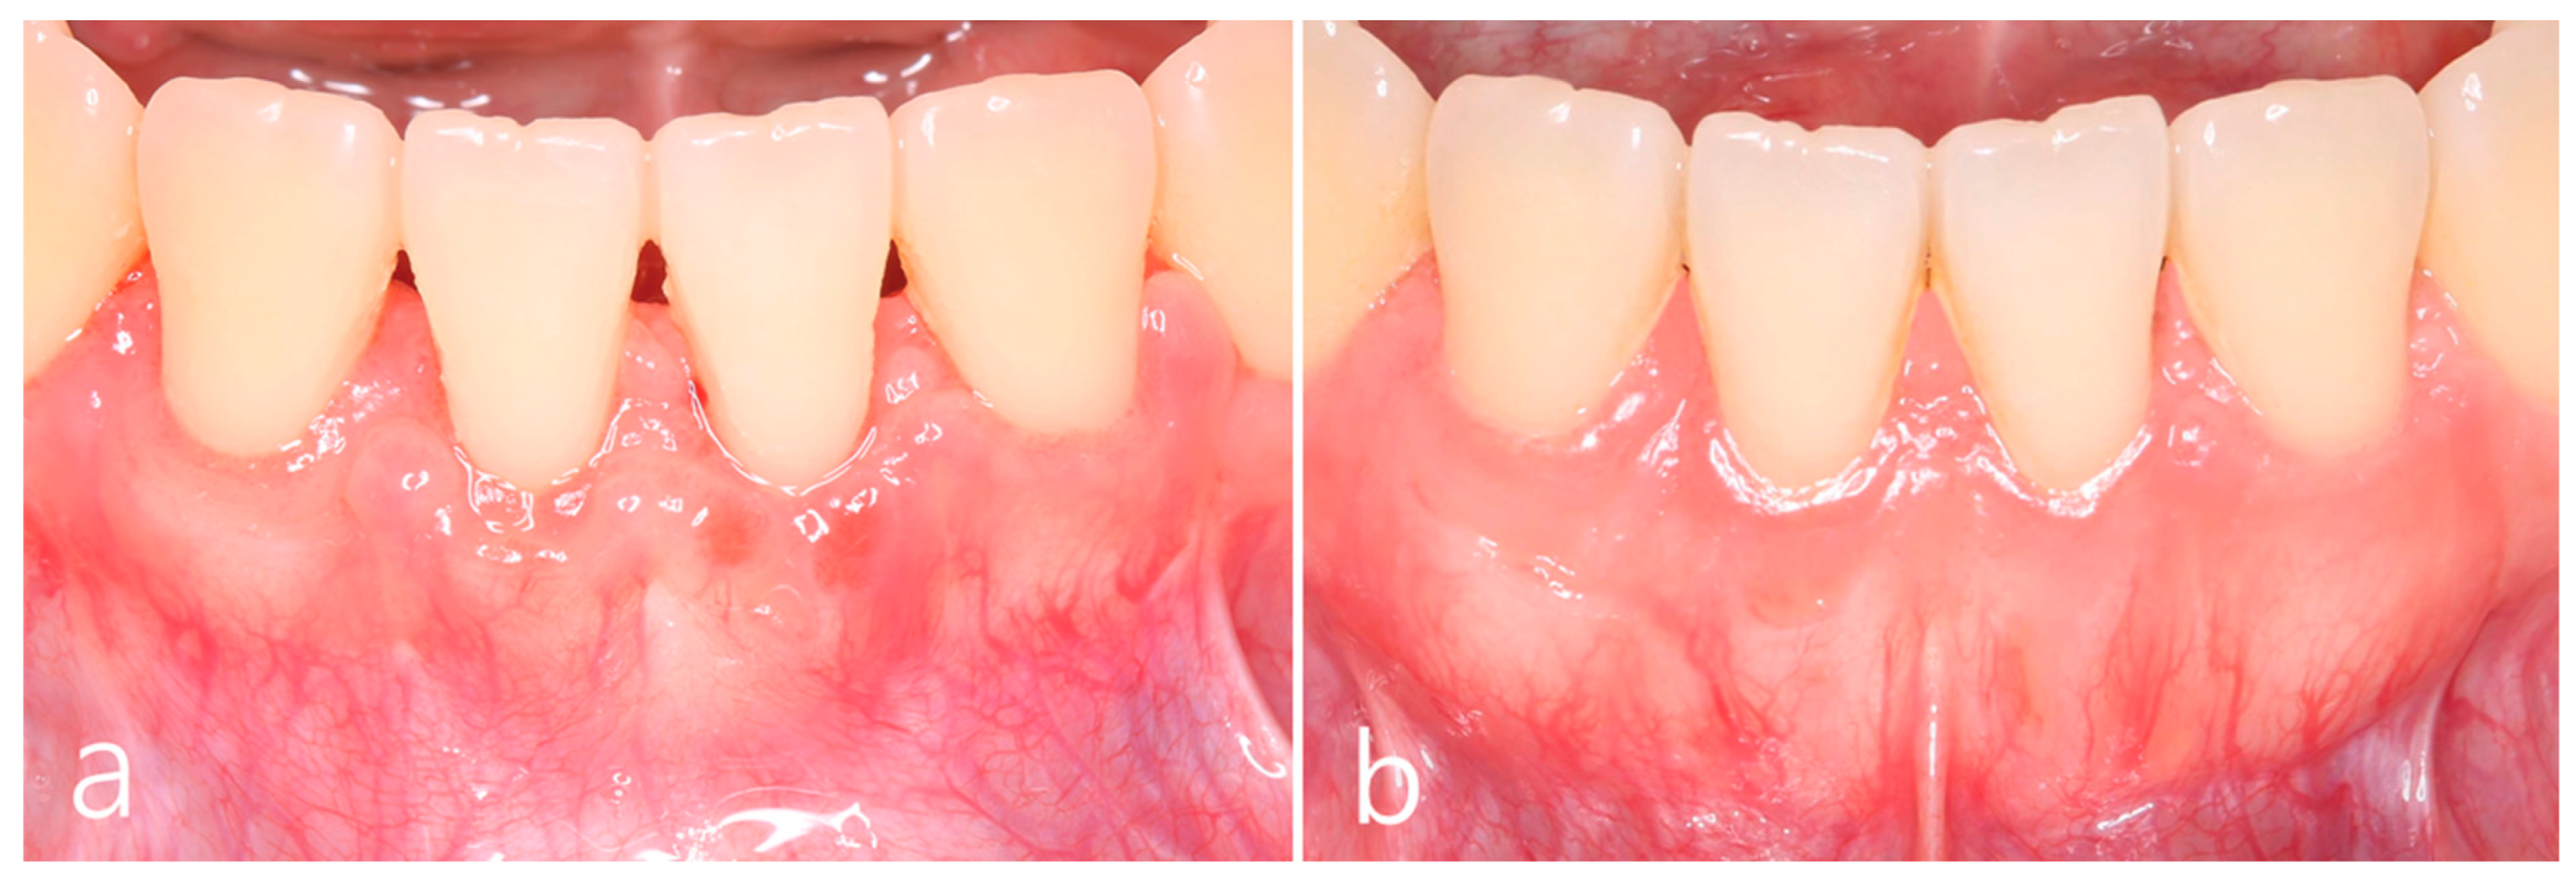

2. Case Report